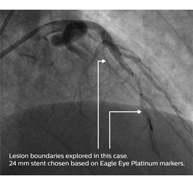

The ADAPT-DES study reported the use of IVUS was associated with a choice of longer stents.1 With IVUS, you can confirm “healthy-to-healthy” landing zones by checking the plaque burden and tissue type at the lesion boundaries.

Philips has a comprehensive suite of imaging devices and modalities to help you see clearly so you can quickly and easily assess lesion morphology with additional imaging modalities, giving you advanced insights. Experience the benefits from Eagle Eye Platinum digital IVUS catheters.

• Three radiopaque markers not offered by other IVUS catheters